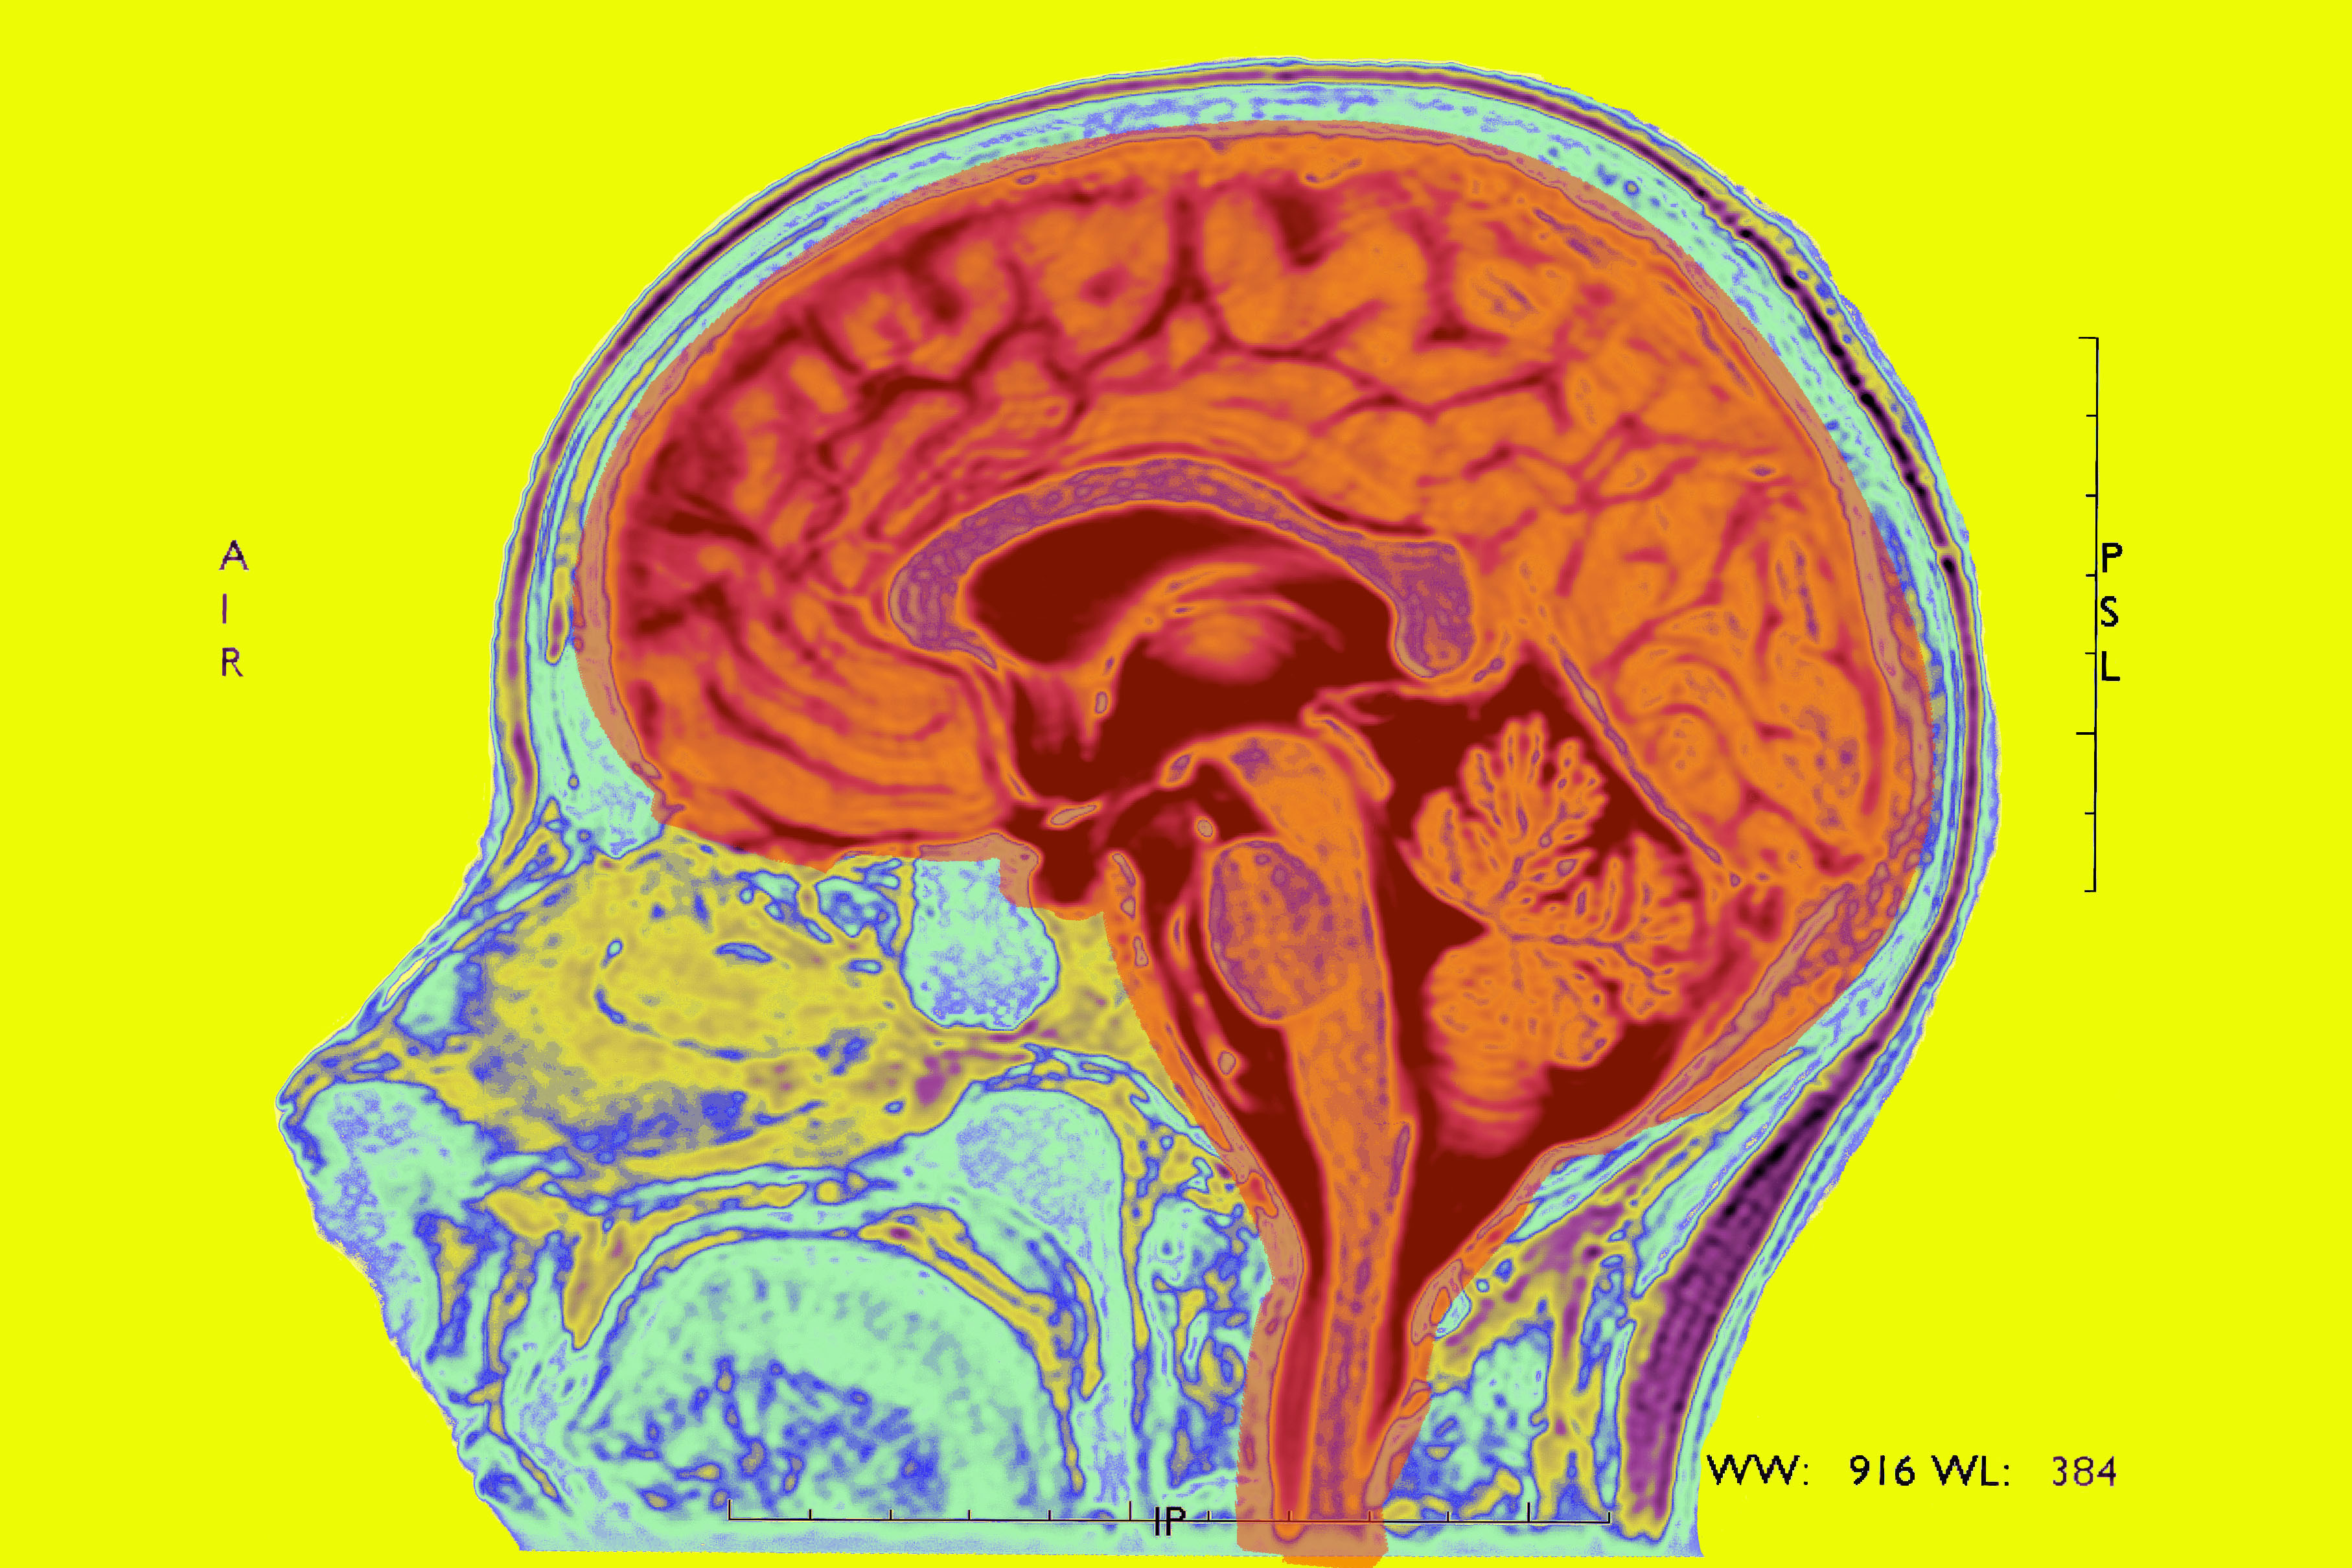

Some researchers are now using functional magnetic resonance imaging scans to track subtle changes in certain brain regions during and after psychotherapy. One day, perhaps, therapists will be able to post before-and-after scans of patients’ brains, highlighting the improvements, much as plastic surgeons do today. But not yet. The studies so far have mainly focused on laying the groundwork by determining which areas of the brain are affected by therapy, says University of Pittsburgh psychiatrist Jay Fournier. Researchers want to pinpoint how the brain changes in each patient as a result of different treatments and what sorts of changes best predict long-term recovery. They also hope to gain a more nuanced understanding of which characteristics in a patient might predict response to different sorts of treatments.